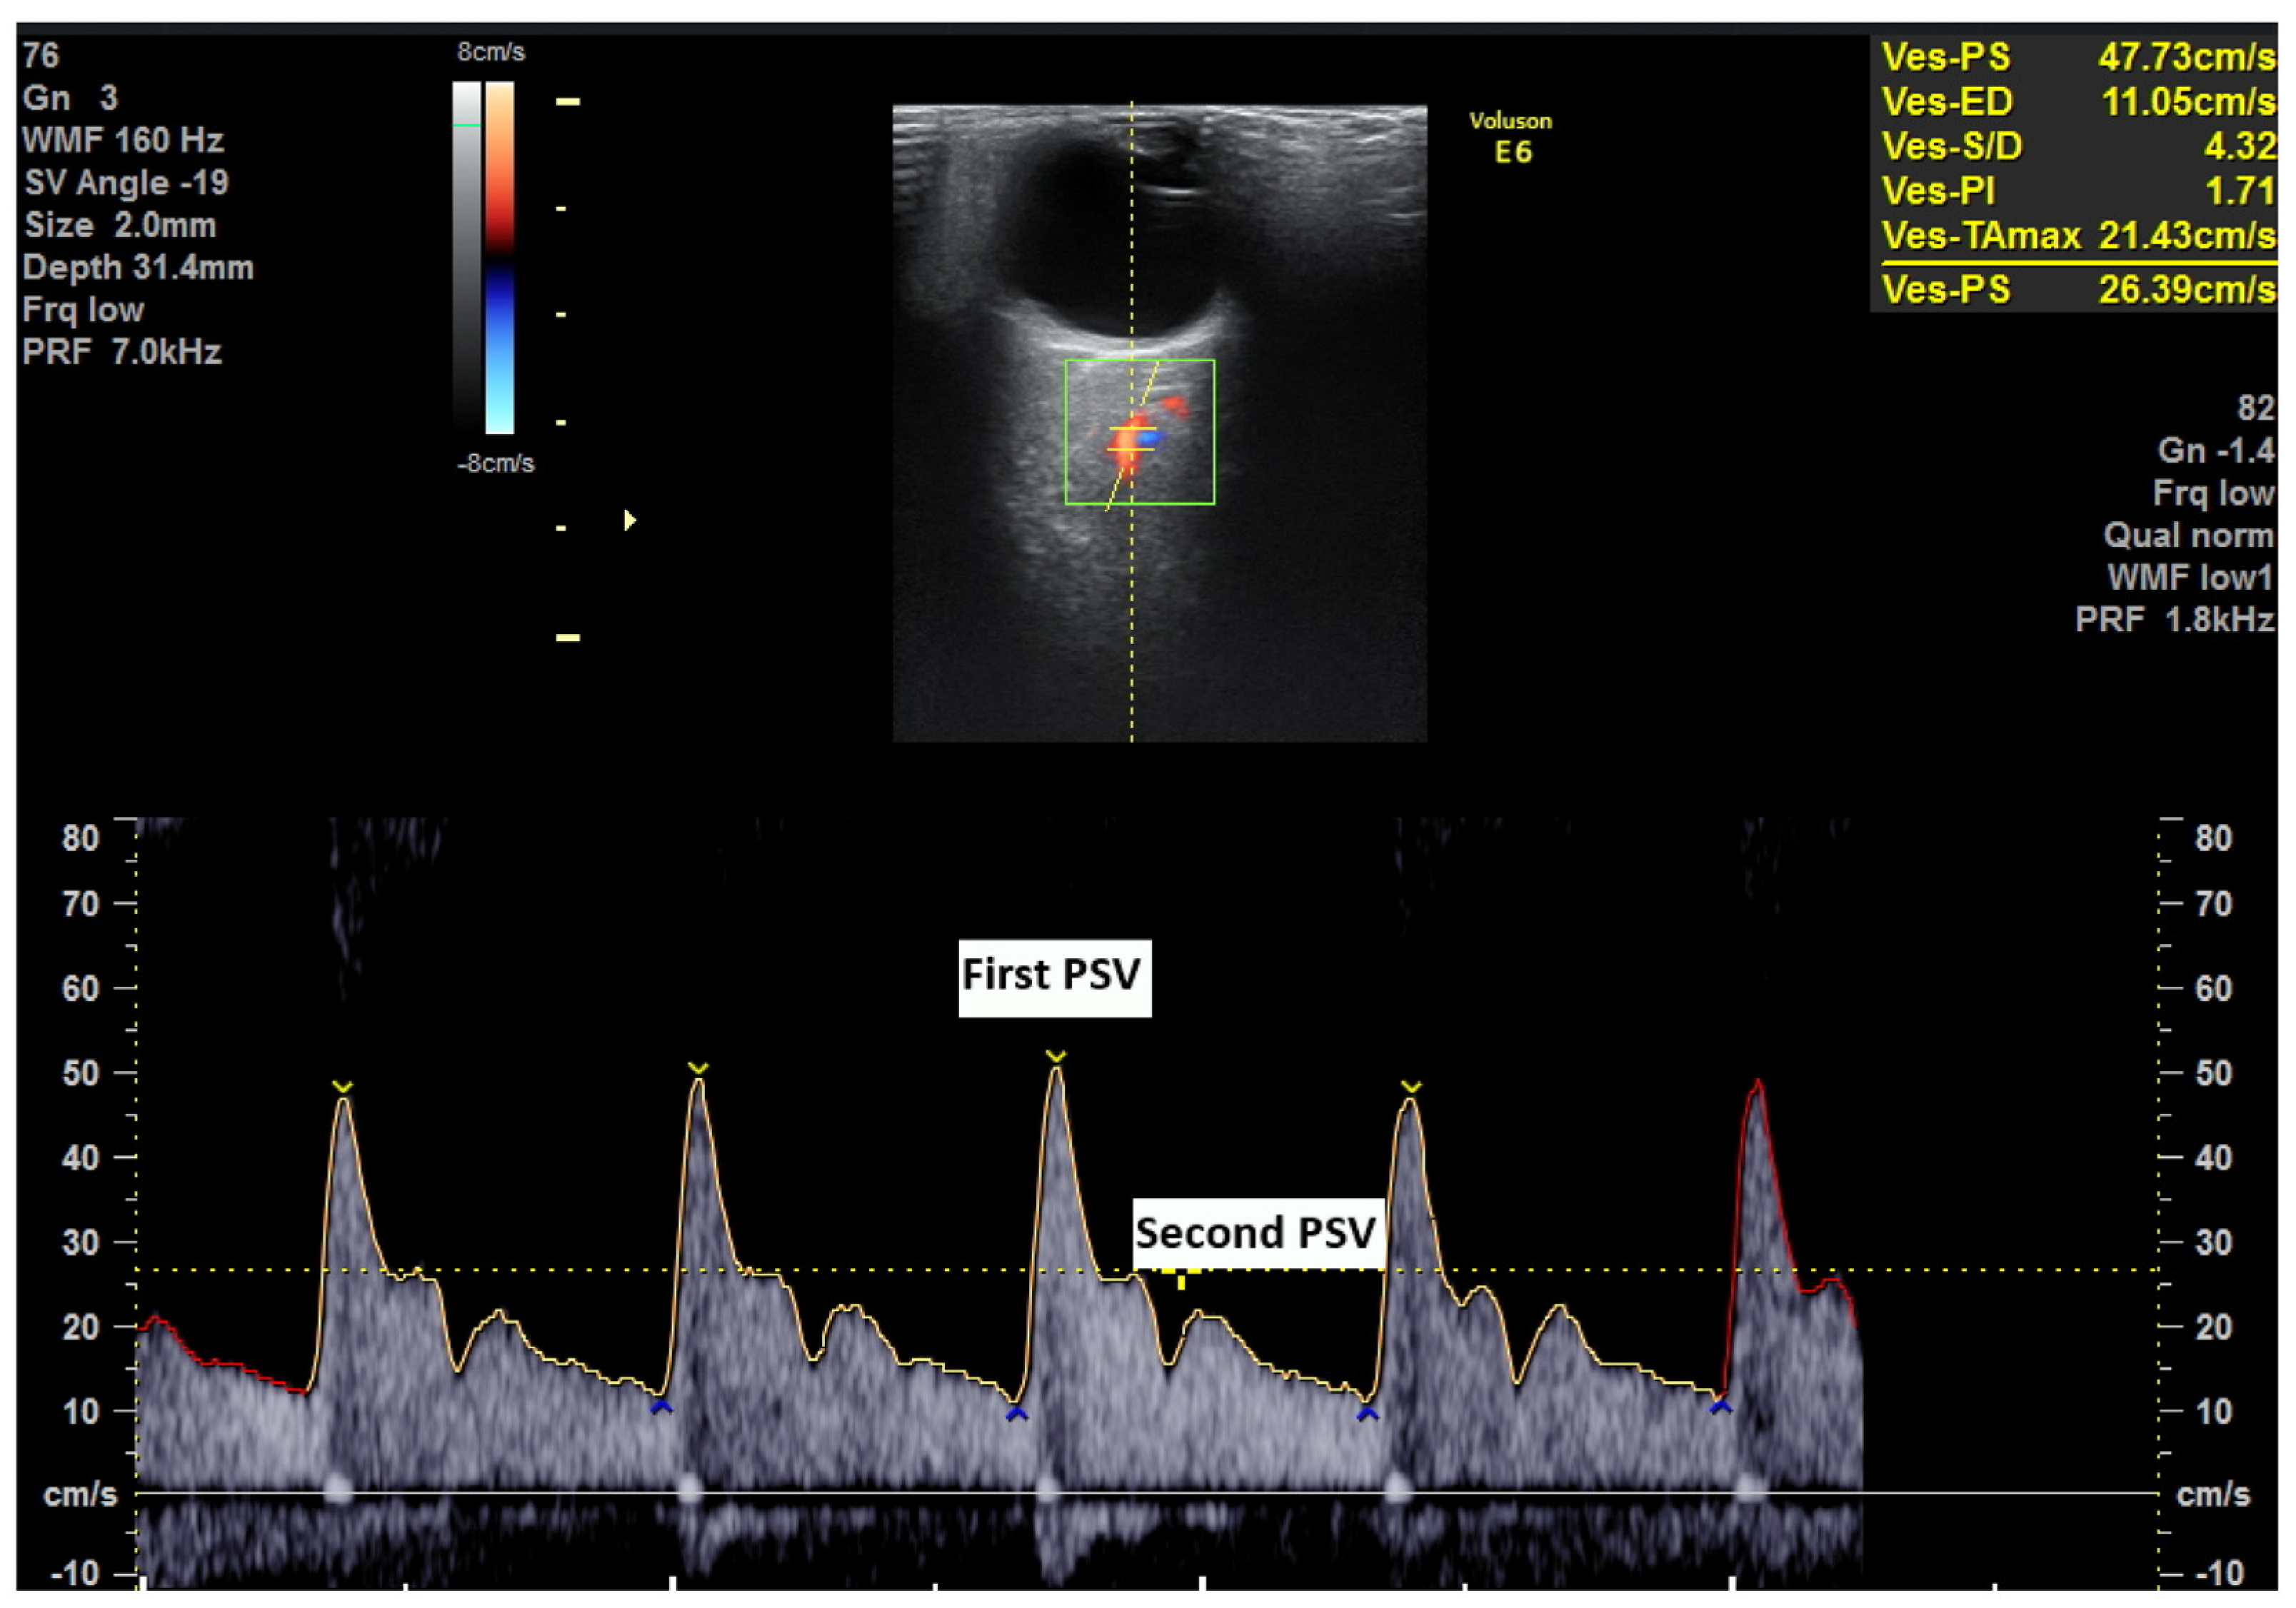

2.2. Ophtalmic Artery Doppler Indices